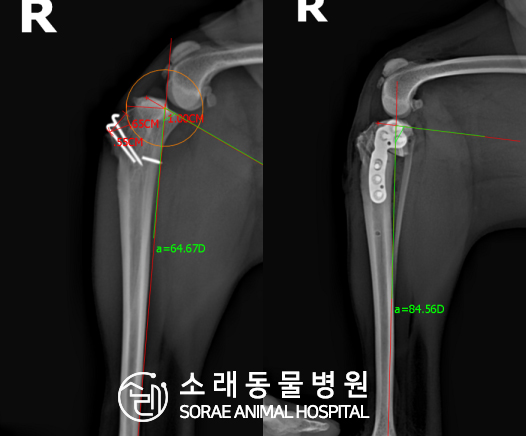

계산식으로 사전에 계획해두었던 플랜에 따라 경골을 절제하고

플레이트와 스크류를 사용하여 임플란트를 적용해 주었습니다.

반대 방향으로 밀려나 어긋나있던 대퇴골과 정강이가

제 자리를 찾으면서 무릎의 각도가 교정된 것을 확인할 수 있습니다